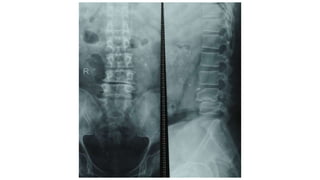

 Chụp X - quang thường: có tam chứng Barr (hình ảnh gián tiếp):

1 - Giảm chiều cao khoang gian đốt sống

2 - Mất ưỡn thắt lưng

3 - Vẹo cột sống thắt lưng.

4. Chẩn đoánthoát vị đĩa đệm 4.1. Chẩn đoán xác định 4.1.2.Chẩn đoán cận lâm sàng  Chụp X - quang thường: có tam chứng Barr (hình ảnh gián tiếp): 1 - Giảm chiều cao khoang gian đốt sống 2 - Mất ưỡn thắt lưng 3 - Vẹo cột sống thắt lưng.  Dịch não tuỷ: đa số trường hợp có kết quả DNT bình thường, hiếm khi có phân ly albumin - tế bào (chỉ trong trường hợp nặng hoặc thóat vị đĩa đệm thể giả u).  Chụp bao rễ thần kinh (hình ảnh gián tiếp)